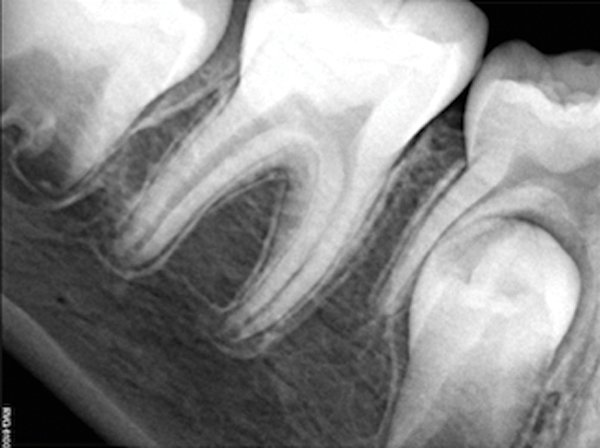

Fig 13. Tooth was asymptomatic at 1-year follow-up. Courtesy of Dr. Guillaume Jouanny.

Figure 13

Fig 14. Contralateral tooth at 1-year follow-up. Courtesy of Dr. Guillaume Jouanny.

Figure 14

Case 2: Pulpotomy

In this case, the tooth tested vital but showed clinical signs of irreversible pulpitis. Treatment with a full pulpotomy was chosen to improve the chances the remaining pulp would survive and remain healthy. The preoperative radiograph in Figure 11 shows extensive caries in the tooth and a slightly widened apical periodontal ligament. A full pulpotomy was performed using the BC putty (Figure 12). After the putty set, a coronal restoration was placed, and an immediate postoperative radiograph was taken and viewed. At the 1-year follow-up, the tooth was asymptomatic, and the radiograph showed continued root development (Figure 13), a healthy apical periodontium, and, importantly, no calcifications in the remaining pulp (as is often seen with a calcium hydroxide therapy). A radiograph taken of the contra-lateral tooth showed similar root development (Figure 14).